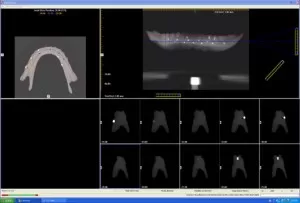

Chụp CT và scan hàm giả bệnh nhân đang đeo

Dựa trên các dữ liệu của phim CT & phần mềm Nobel Clinician để lên kế hoạch điều trị:

Tuy nhiên nhóm bác sỹ nhận thấy sống hàm vùng cằm tại các vị trí răng 32, 35, 42, 45 cần đặt implant không bằng phẳng, nhỏ và nhọn.

Do đó nhóm Bs quyết định phương án: gọt thấp xương hàm vùng cằm để gia tăng kích thước đường kính của các implant và tạo thuận lợi cho phục hình sau này.